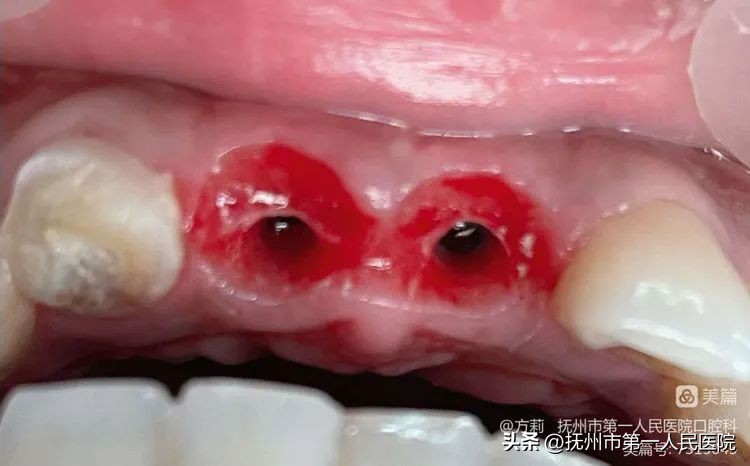

第一步:术前拔牙

2021年5月19日进行11、21拔除术!牙根粗大且较长致使拔牙窝也较为粗大,即刻种植时容易因为唇侧阻力小而导致植体偏向唇侧以致种植骨量不足导致即刻种植失败!因时间问题,推迟两天种植!